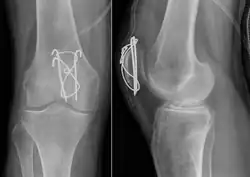

Surgery

Most patella fractures are transverse or comminuted, hence the quadriceps mechanism is disrupted and they are treated by a combination of wires in a tension band construct. This unites the fractured bones, reconstructing the straightening mechanism of the leg.[5][6]